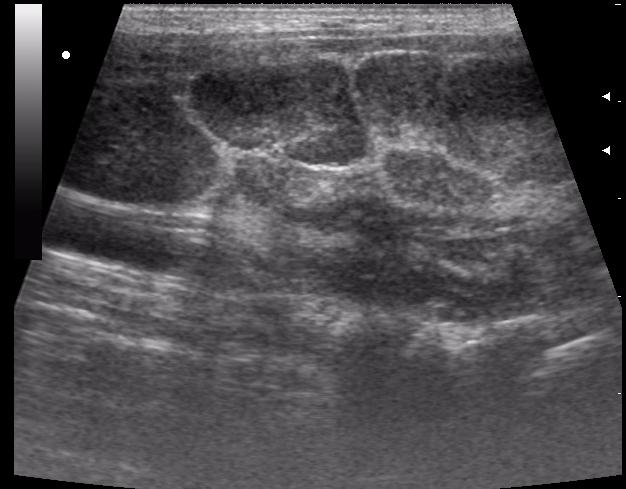

лимфоузел в правой подчелюстной области

лимфоузел в левой подчелюстной области